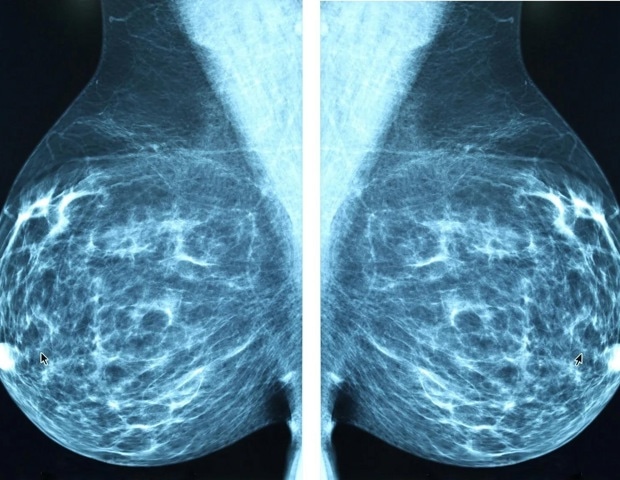

Около трех четвертей всех случаев рака молочной железы являются ER-положительными. Это означает, что опухоли богаты молекулой, известной как рецептор эстрогена, «питающейся» эстрогеном, циркулирующим в организме. Этим женщинам обычно предлагают антиэстрогены, лекарства, которые снижают уровень эстрогена и, следовательно, лишают рак эстрогена и подавляют его рост. Однако снижение уровня эстрогена может вызвать симптомы, подобные менопаузе, включая приливы, боли в суставах и мышцах, а также потенциальную потерю костной массы.

В исследовании PIONEER женщин в постменопаузе с ER-положительным раком лечили антиэстрогеном с мегестролом, имитирующим прогестерон, или без него. После двух недель лечения у тех, кто получал комбинацию, наблюдалось большее снижение скорости роста опухоли по сравнению с теми, кто получал только антиэстроген.

В общей сложности 198 пациентов были набраны в десяти больницах Великобритании, включая больницу Адденбрука в Кембридже, и рандомизированы в одну из трех групп: одна группа получала только летрозол; одна группа получала летрозол вместе с 40 мг мегестрола ежедневно; а третья группа получала летрозол плюс гораздо более высокую суточную дозу мегестрола – 160 мг. В этом исследовании «окна возможностей» лечение проводилось за две недели до операции по удалению опухоли. Процент активно растущих опухолевых клеток оценивался в начале исследования, а затем еще раз перед операцией.